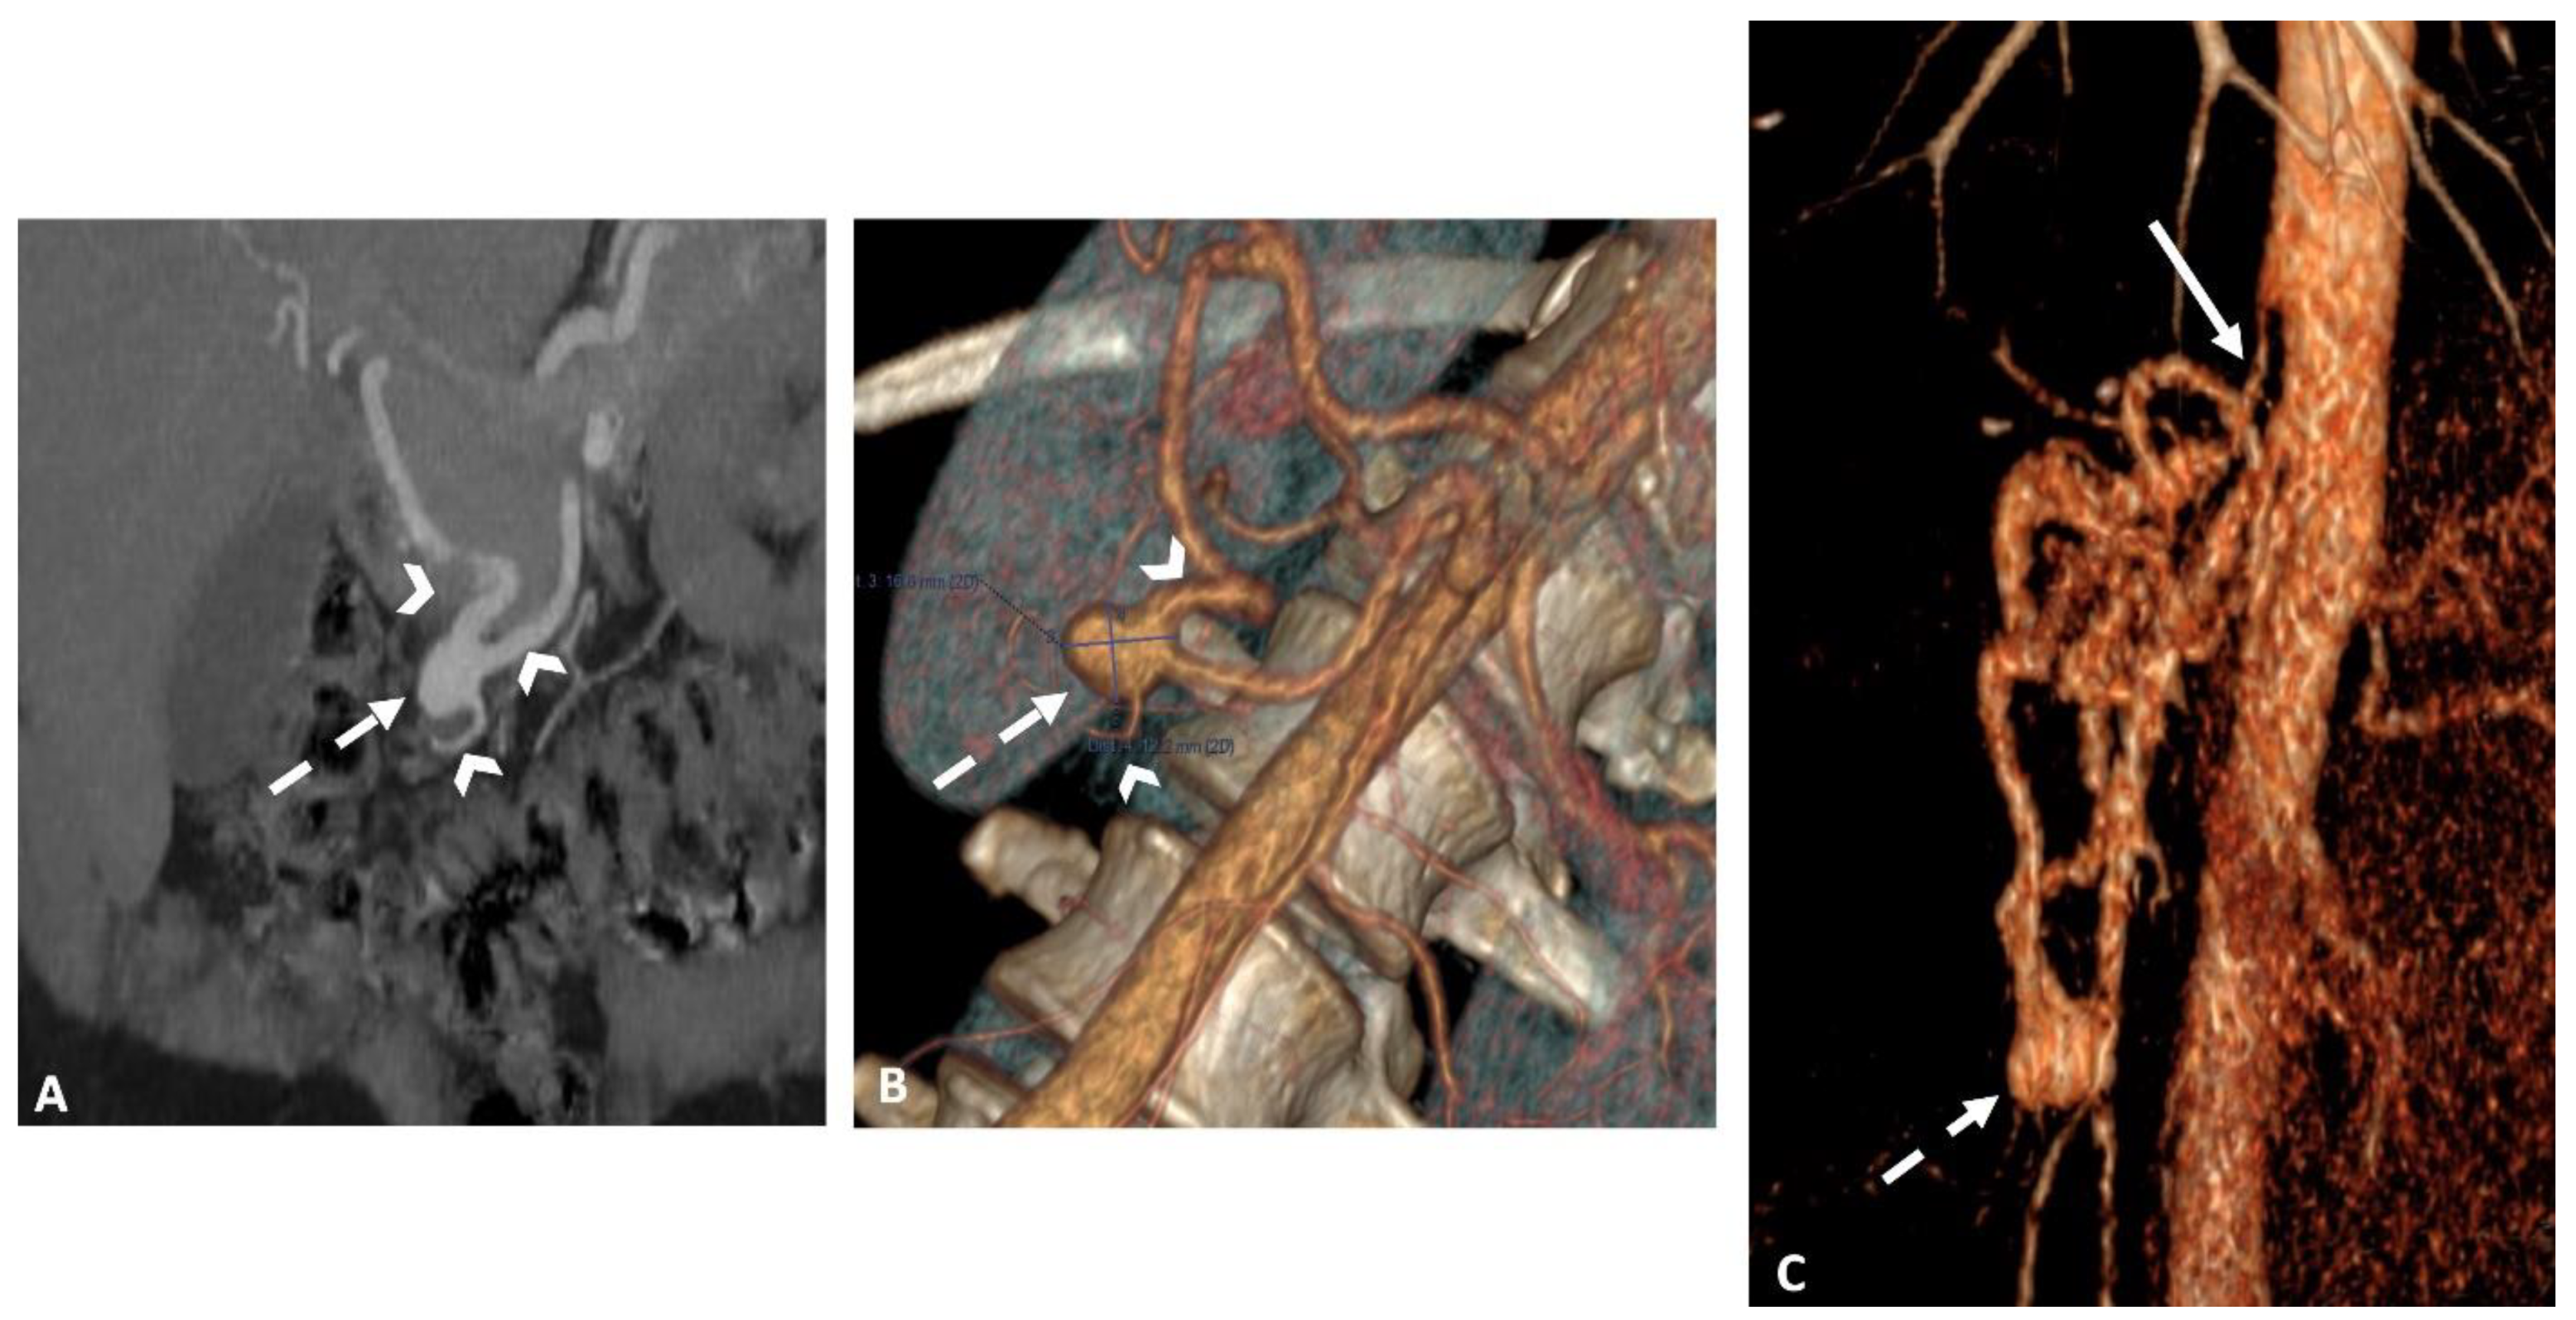

In 10 cases (43%), the anchoring technique in another non-target branch of the SMA was used, enabling stability for long sheath, catheter, microcatheter, and guidewire placements and overcoming tension in the coaxial equipment (Figure 2).

Patients were followed for a median of 16 months [2-48 months]. The clinical success rate was 100%. At the one-month follow-up, imaging confirmed the complete exclusion of the embolized aneurysm in all patients (Figure 3).

Figure 3. Superior mesenteric arteriography showing an aneurysm of the antero-inferior PDA before (solid white arrow/A) and after embolization (B) using “sandwich” technique and exclusion of inflow and outflow arteries (arrowheads/B). Note the reinjection via collaterals into splenic and hepatic arteries (dashed arrows). Figure C shows an MRI angiography in the arterial phase with subtraction in a coronal view with maximum-intensity-projection reformatting, confirming the total exclusion of the aneurysmal sac on the 1-month after embolization.